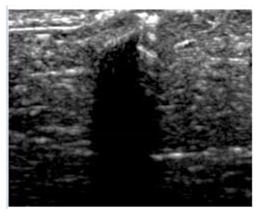

2.6. Echogenicity

To measure the echogenicity of each aerogel type, two ROIs were strategically selected from each B-mode image and indicated with a clear boundary in Figure 3. These correspond to top ROI which represents the implant area and bottom ROI representing the posterior shadowing region. Figure 3a shows these two regions in the absence of any aerogel implants while Figure 3b captures the same regions in the presence of an implant (ROI-3 and ROI-4). In each case, the Mean Pixel Intensity (MPI) of the two ROIs was measured using the measure function in ImageJ. MPI of ROI-1 and ROI-2 formed the baseline for the percentage change calculation, which was arrived at using Equation (4a,b)—Table 2. Based on the value of the ROI, aerogels were classified as hyperechoic, isoechoic, hypoechoic, and anechoic and summarized in Table 3 where ΔE can vary between −100% and +255%. Acoustic impedance mismatch between the aerogels and tissue was calculated using a percentage difference method, indicated in Table 2 by Equation (6).

Figure 3.

(a) Selection of ROI-1 and ROI-2 in the B-mode image of the muscle without implants. (b) Selection of ROI-3 and ROI-4 in the B-mode image with aerogel implants.

Table 3.

Table showing the echogenicity classification used in this study with US images of aerogels inserted SC and SM being compared to US images of the tissue.